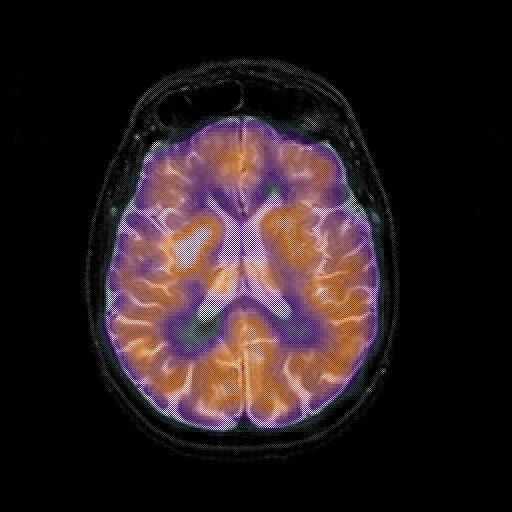

overlay 1: Slice 31

Slice 31

MRCBFCBF with

T1PDT2T1PDT2